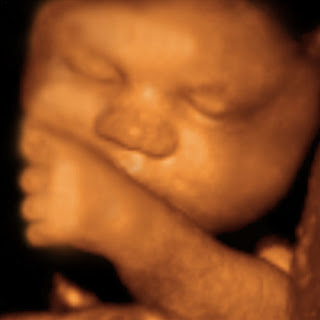

| 4D OBSTETRİK | RENAL ARTER RDUS |

| SUPRAPUBİK USG | 4D OBSTETRİK USG |

DÖRT BOYUTLU RENKLİ OBSTETRİK DİJİTAL CİHAZLARIMIZLA BEBEĞİNİZİN CANLI DVD ÇEKİMLERİ HASTALARIMIZA VERİLMEKTEDİR.

| 4D OBSTETRİK | RENAL ARTER RDUS | ||

| SUPRAPUBİK USG | 4D OBSTETRİK USG | ||